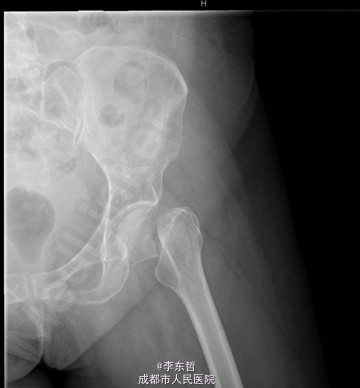

患者女,61岁,因“摔伤致左髋疼痛伴活动受限4+天”入院。患者自诉4+天前在浴室里不慎滑倒,左髋部着地,当时感左髋部剧痛,伴有活动受限,不伴有恶心呕吐、头痛头昏等不适。患者随即被家属送至当地医院,完善X线片后提示左股骨颈骨折,给予对症支持治疗后,患者家属为求进一步诊治,转至我院急诊科,以左股骨颈骨折送入我科。

查体:T:37.2oC,P:96次/分,R:22次/分,BP:113/62mmHg。神志清楚,无病容,皮肤巩膜无黄染,全身浅表淋巴结未见肿大。颈静脉正常。心界正常,心律齐,各瓣膜区未闻及杂音。胸廓未见异常,双肺叩诊呈清音,双肺呼吸音清,未闻及干湿啰音及胸膜摩擦音。腹部外形正常,全腹柔软,无压痛及反跳痛,腹部未触及包块,肝脏肋下未触及,脾脏肋下未触及,双肾未触及。双下肢无水肿。专科查体:视:双下肢不等长,左下肢外旋畸形,左髋肿胀,周围皮肤未见红肿,溃疡,窦道,瘘管等形成;触:双下肢皮肤感觉正常,末梢循环良好,足背动脉可扪及,左髋肿胀,触压痛明显,股骨颈叩击痛阳性,未闻及骨摩擦音及摩擦感;动量:双下肢肌力及肌张力正常,右髋、双膝、踝关节活动度良好,左下肢较右侧缩短约2cm,左髋因疼痛拒动。 辅助检查X片示:左股骨颈骨折,远断端向上方错位,左髋关节在位。骨盆骨质疏松。